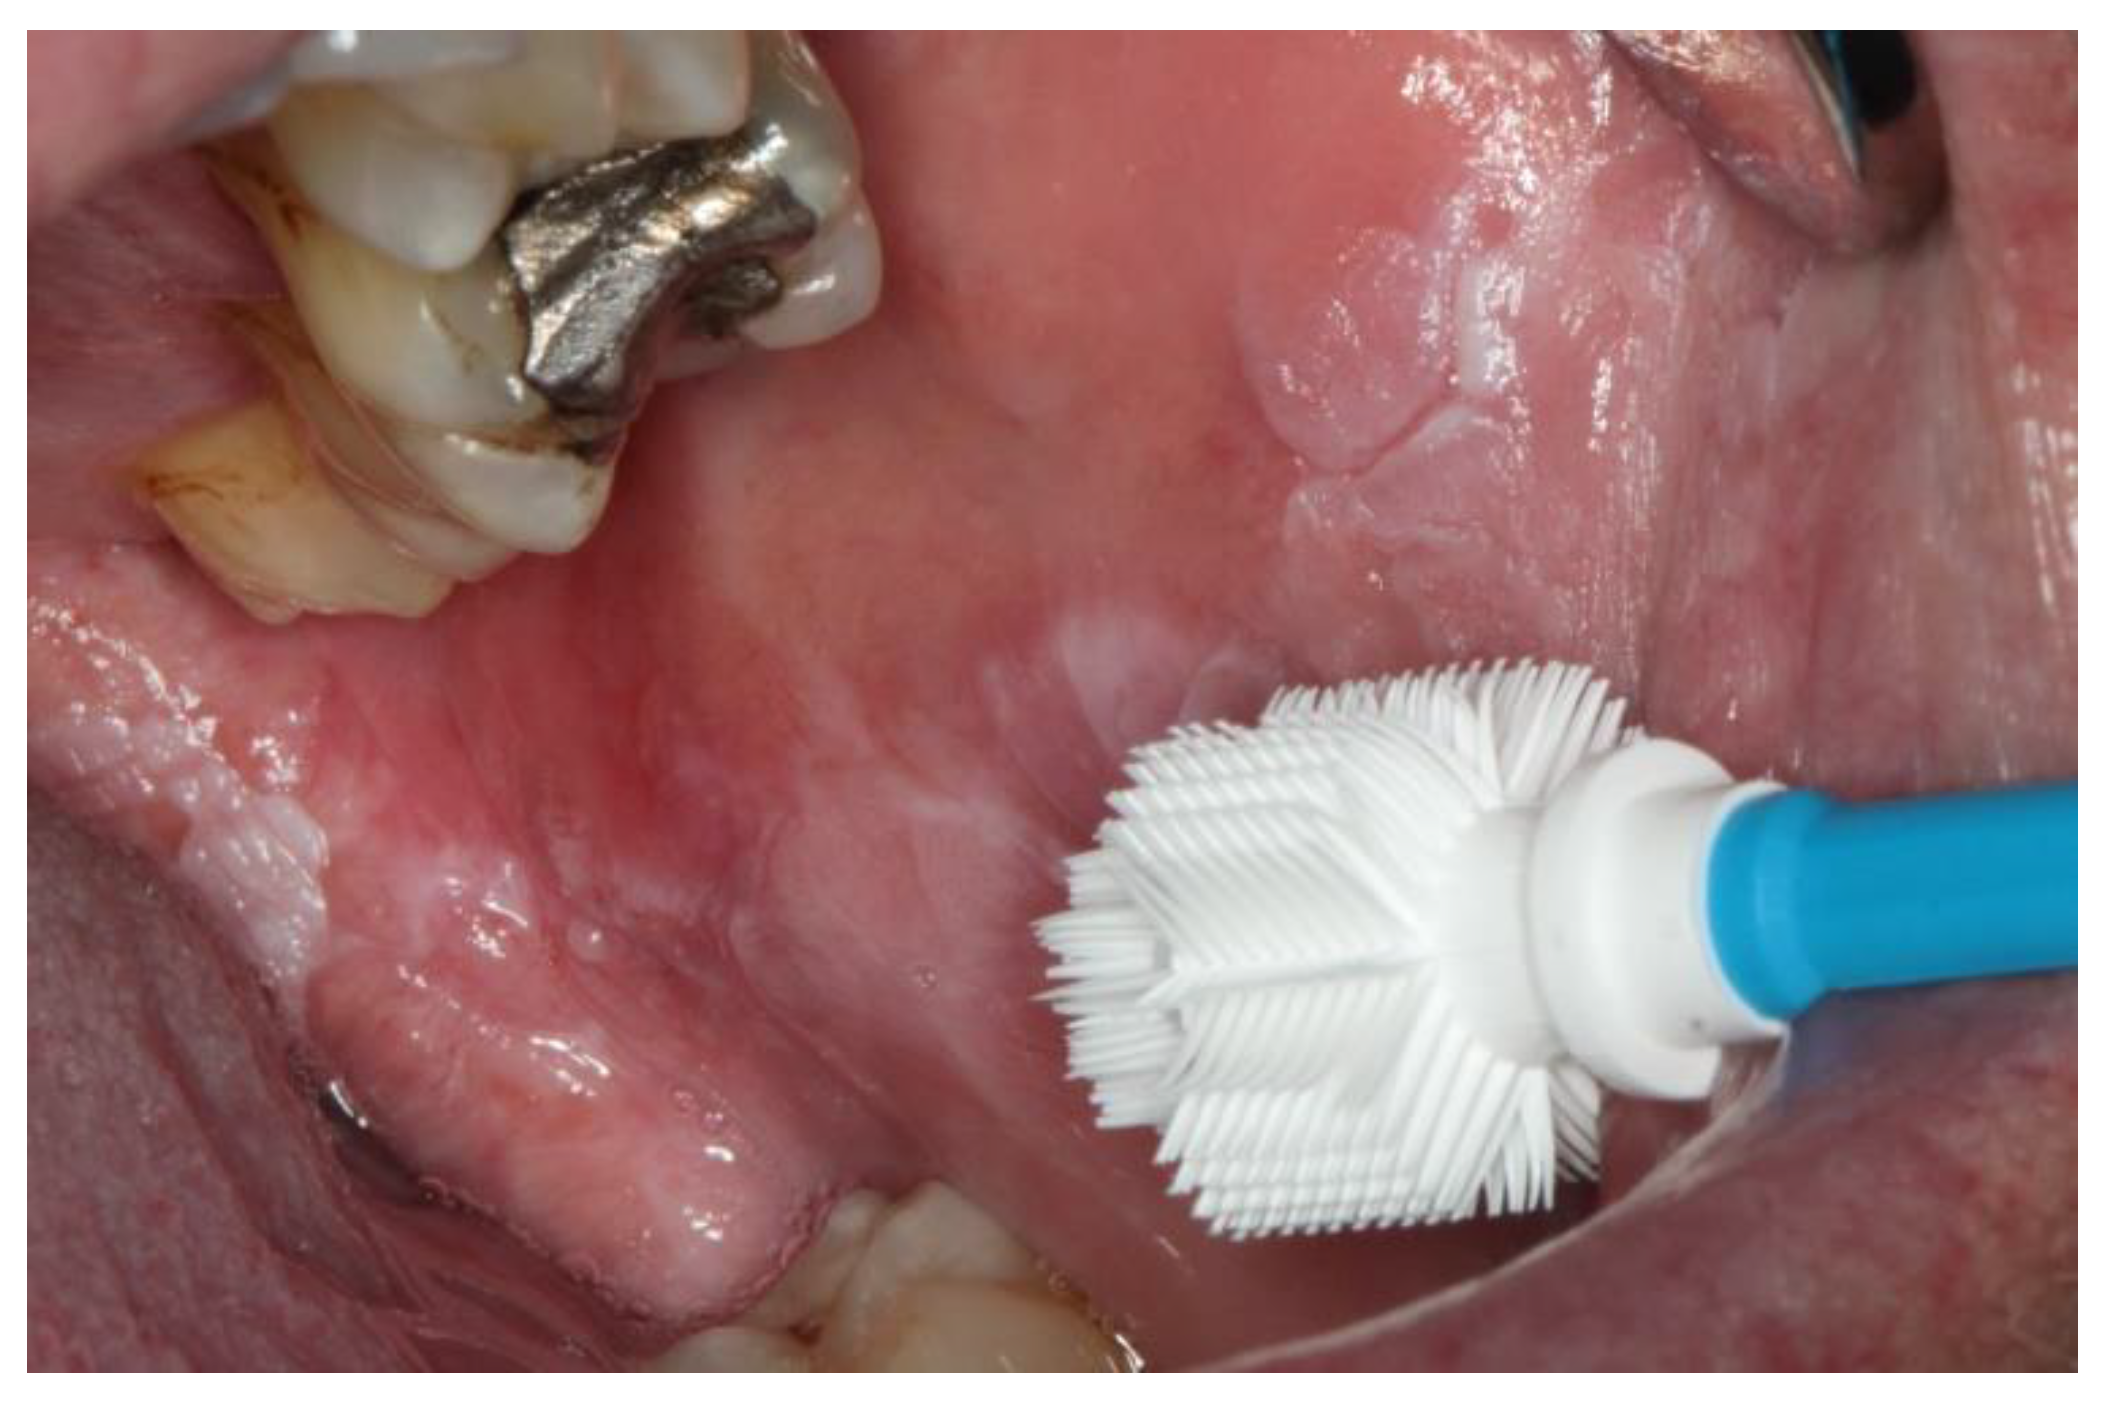

- Kujan, O.; Pemberton, M.N.; Schwarz, M.; Sloan, P. Evaluation of an innovative oral brush for potential applications using liquid based cytology. J. Oral Sci. 2018, 60, 45–50. [Google Scholar] [CrossRef] [PubMed]

- Olms, C.; Hix, N.; Neumann, H.; Yahiaoui-Doktor, M.; Remmerbach, T.W. Clinical comparison of liquid-based and conventional cytology of oral brush biopsies: A randomized controlled trial. Head Face Med. 2018, 14, 9. [Google Scholar] [CrossRef] [PubMed]